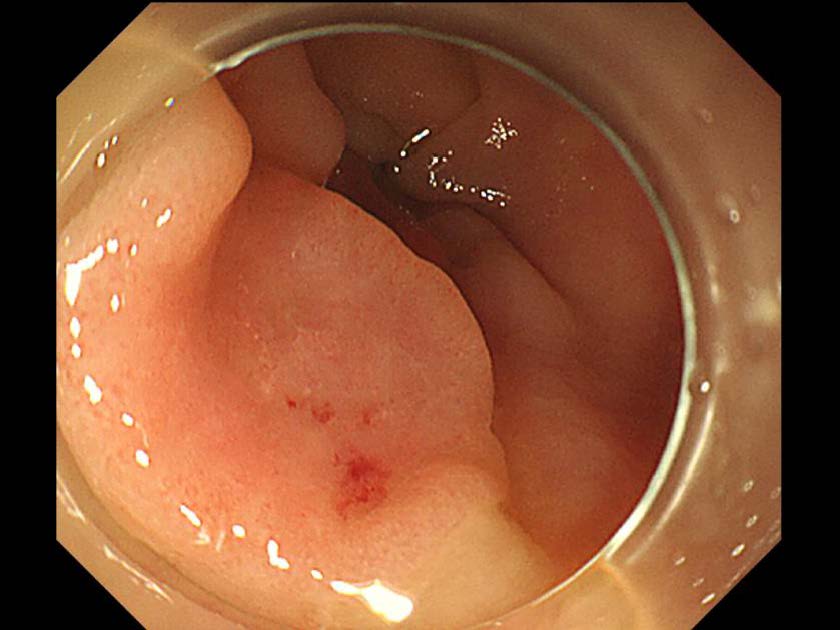

消化管Mapping~大腸~ 2021.10.27

消化器センター 消化器内科

消化管Mapping

消化管Mapping~大腸~

内視鏡検査・治療